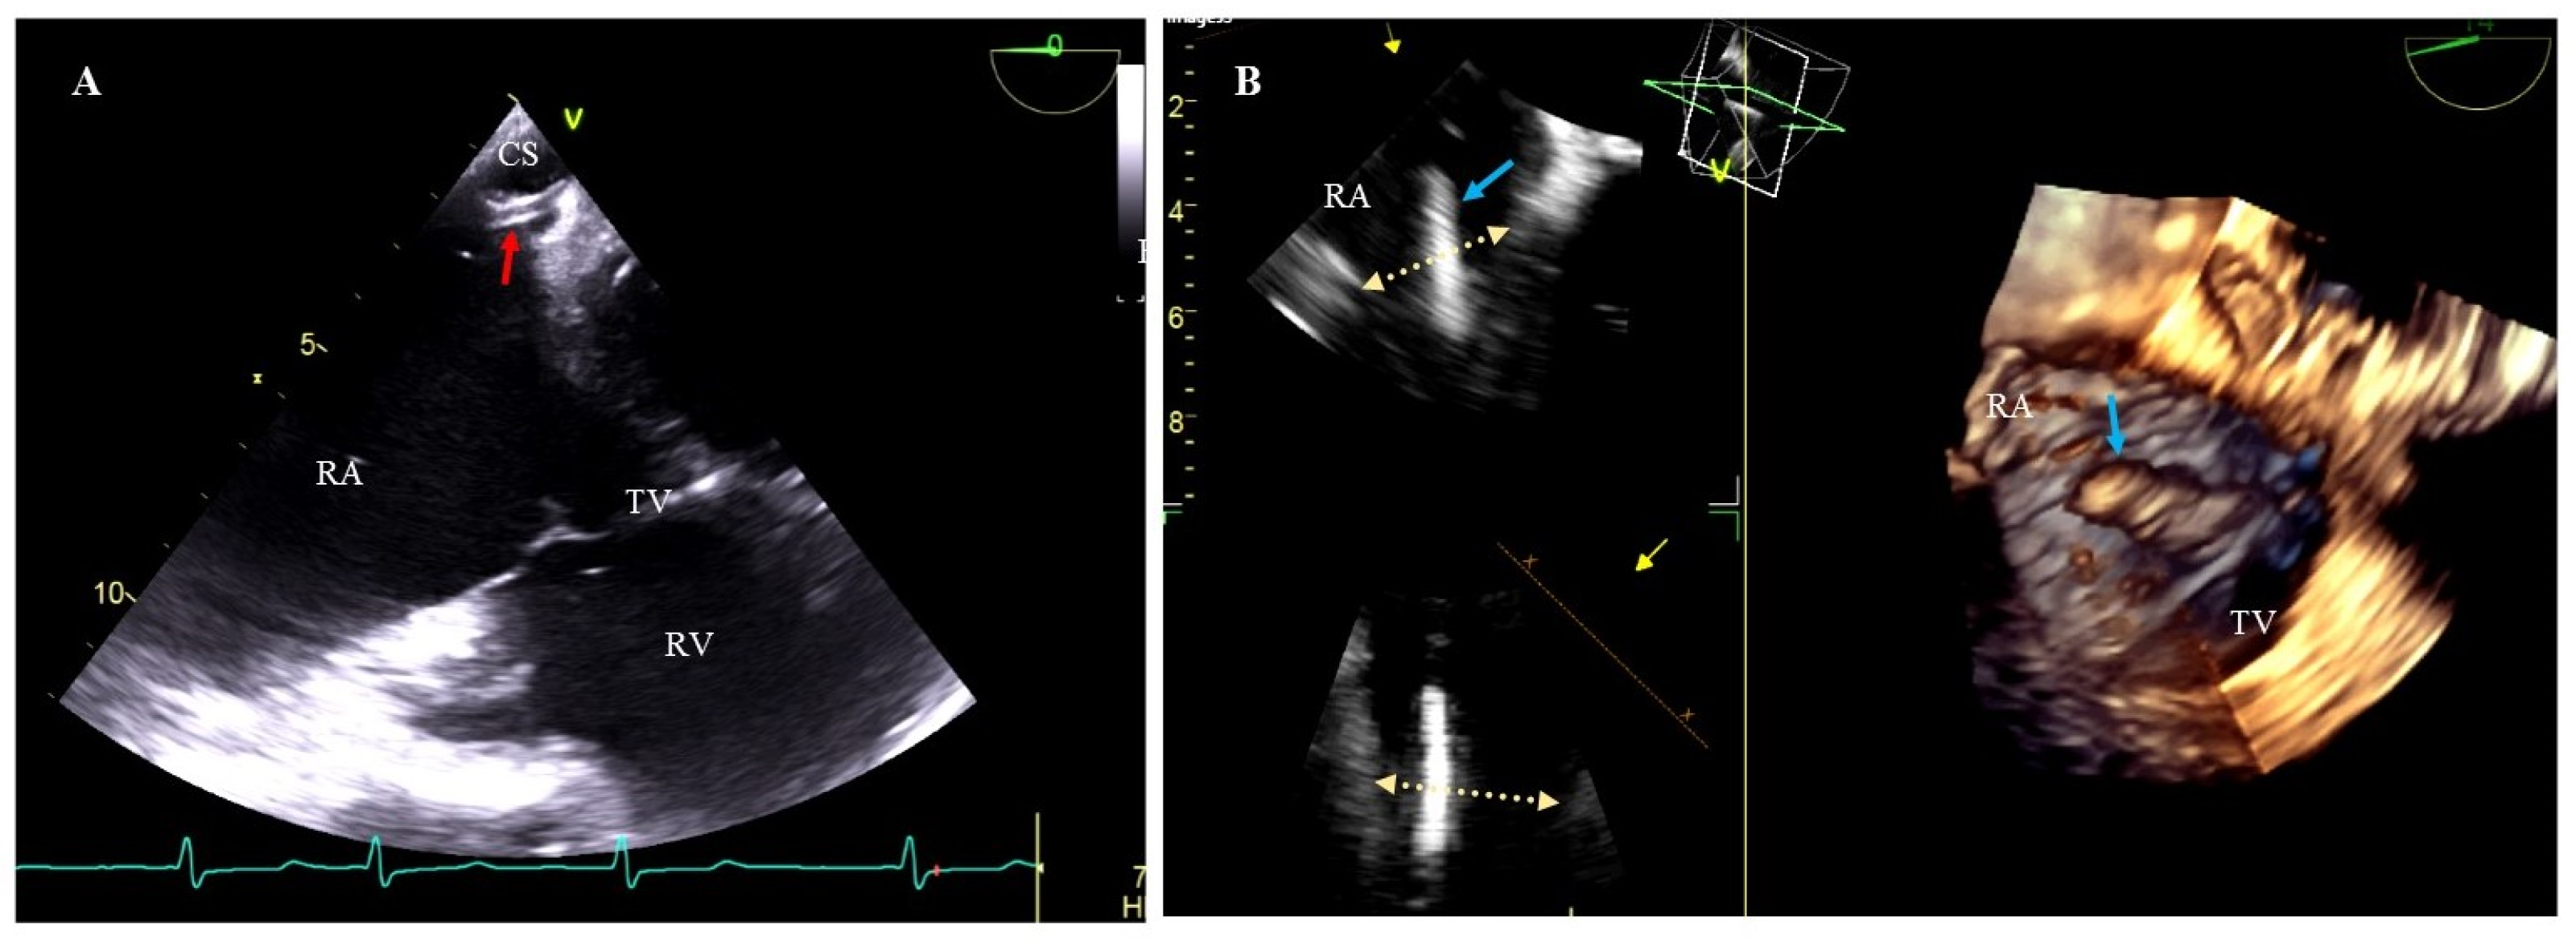

Consideration should also be given to the additional use of transesophageal echocardiography (TEE) when inserting new leads after TLE. TEE facilitates the monitoring of the intubation process of the coronary sinus, thus shortening the time of fluoroscopy, and if high-voltage lead is required, TEE can help accurately assess the relationship between the proximal coil end and the level of the valve and leaflets (Figure 2).

Figure 2.

Additional use of TEE at new lead implantation during TLE. (A) 2D TEE images- lower esophageal view. A catheter (red arrow) was inserted into the coronary sinus (CS) under X-ray and TEE guidance. (B) 3D TEE images—mid-esophageal view. The coil (blue arrow) protrudes into RA above the tricuspid valve level (yellow arrows). RA—right atrium, RV—right ventricle, TV—tricuspid valve.

TEE monitoring during lead extraction procedures has become the standard clinical approach whose importance cannot be overestimated. In patients undergoing TLE with subsequent upgrade it allows for a more accurate assessment of the location of RV lead tips, and if implantation of CS lead for left ventricular pacing is required, TEE is used for navigation during insertion of the delivery catheter into the CS ostium (Figure 2) [27,36,37].